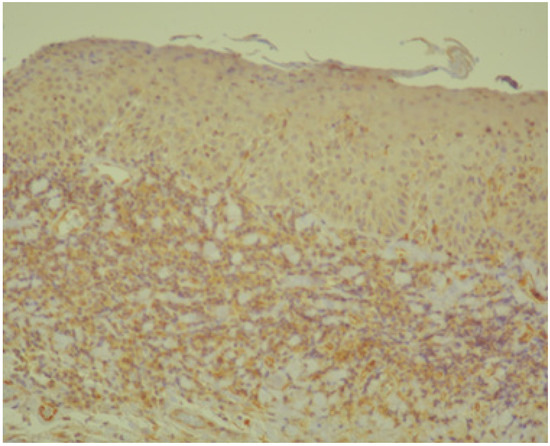

3.1. Histopathology and Immunohistochemistry

2.2. Histopathology and Immunohistochemistry